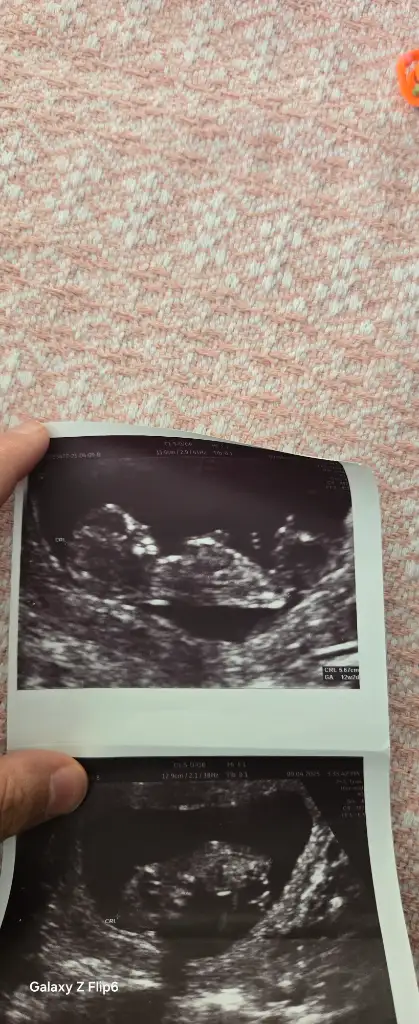

Lütfen bana bakarmısınız,? 6 hafta 4 gunluk bebisim

Eklentiler

• WhatsApp Image 2025-09-10 at 15.42.56 (2).webp

WhatsApp Image 2025-09-10 at 15.42.56 (2).webp

53,1 KB · Görüntüleme: 9

• WhatsApp Image 2025-09-10 at 15.42.56 (1).webp

WhatsApp Image 2025-09-10 at 15.42.56 (1).webp

47,5 KB · Görüntüleme: 8

• WhatsApp Image 2025-09-10 at 15.42.56.webp

WhatsApp Image 2025-09-10 at 15.42.56.webp

47,2 KB · Görüntüleme: 8